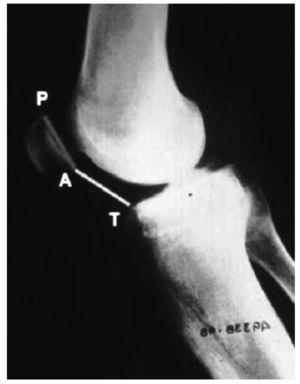

La altura rotuliana se estudió mediante el método de Caton6 (fig. 1). La inclinación rotuliana se valoró por el método que describieron Maldague y Malghem7. El ángulo de congruencia y el ángulo del surco fueron medidos en las proyecciones axiales tomadas a 45º de flexión, según la descripción clásica de Merchant8 (fig. 2), mientras que ángulo e índice patelofemoral se obtuvieron a 20º de flexión, usando la técnica de Laurin9 (fig. 3).

Figura 1.Índice de Caton.